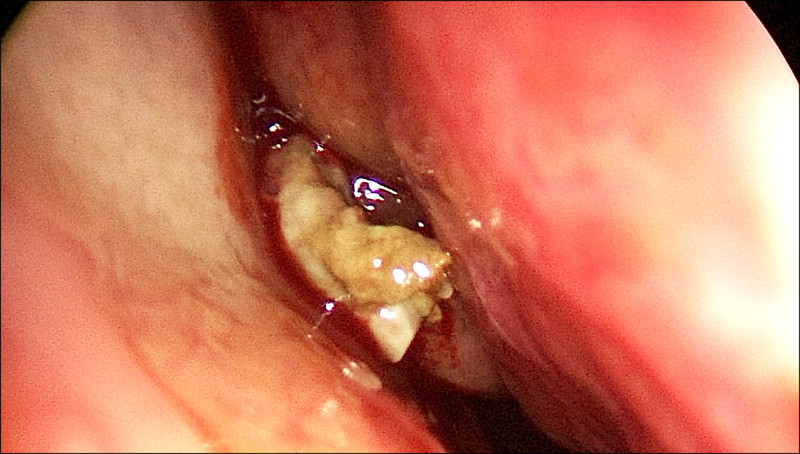

56歲的林小姐半年來飽受鼻塞、咳嗽有痰偶爾帶血絲,服用多輪抗生素治療未改善,經轉介前來就醫,內視鏡檢查確認是鼻竇炎問題,結合電腦斷層檢查發現,引起鼻竇炎的罪魁禍首不是細菌,而是感染了黴菌!(圖1)黴菌在她的鼻竇裡堆積成黏土狀(圖2),即使鼻沖洗也難以清除,須手術打開鼻竇、完整移除黴菌塊,手術後她不需使用抗黴菌藥物即可順利康復,也終於放下心中的大石。

黴菌球不是腫瘤,不會侵蝕鼻竇,但會在鼻竇中逐漸堆積、乾燥凝結,形成一團像黏土般的硬塊,無法自行排出。黴菌球內常有鈣化,影像學檢查上會呈現亮白如石頭般的特徵(圖3)。

治療方面,黴菌球因常伴隨細菌感染,單靠抗生素可能稍有改善但無法根治;抗黴菌藥物也無法深入團塊內部,鼻沖洗更無法徹底清除,所以,最有效的治療方式是以微創內視鏡手術(ESS)打開鼻竇開口,徹底移除黴菌塊,手術傷口小、恢復快,復發率低。